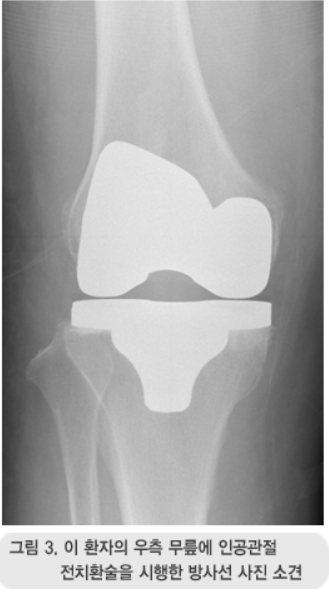

무릎 인공관절 수술은 손상된 관절을 금속이나 특수 플라스틱 재질의 인공관절로 바꾸는 수술이에요. 대표적으로 퇴행성 관절염이 심해져 약물이나 물리치료로는 더 이상 효과를 보기 어려운 경우에 시행돼요.

무릎 인공관절 수술을 받게 되면 가장 큰 장점은 통증에서 해방된다는 거예요. 걷기, 계단 오르내리기, 가벼운 운동까지 가능해지고, 휘어진 다리가 곧게 펴지는 효과도 있어요.

많은 환자들이 수술 전 무릎이 잘 펴지지 않거나 70도 이상 구부리기 힘들어하는 경우가 있는데요, 수술 후에는 대부분 100도 이상 구부릴 수 있고, 심한 경우가 아니면 생활에 큰 제약 없이 움직일 수 있게 돼요.